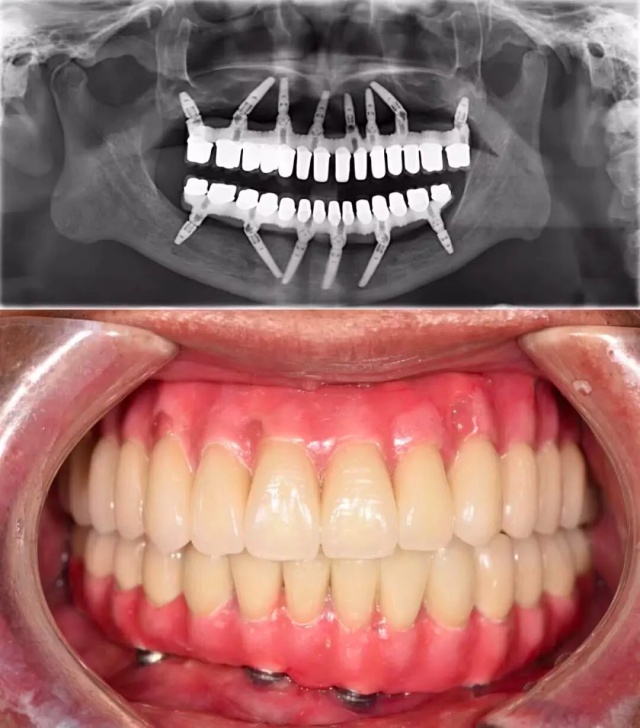

殊不知全*活口**动义齿,不仅功能比天然牙齿相差一大截,咀嚼效力不高,使用也不方便。全口种植义齿也是一种选择,可以较好地恢复咀嚼功能。

但现实是,并不是每个无牙患者,都拥有「口腔里开一辆奔驰」的财力。

价格高昂种植义齿 ↓↓↓